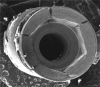

Implants with internal hex connections are more prone to failure at the connection than those with external hex connections.28 This is related to the thickness of the metal at the thinnest point between the internal surface of the interface and the external surface at the crestal area of the implant. When overloaded, implants with an internal hex connection may present with fractures at the points of the hex.29 These points are where the metal is the thinnest at the crestal portion of the implant and where stress is concentrated during overloading. This is less problematic in wider diameter implants because the metal is thicker in this area of the implant; however, in standard or narrow diameter implants, fracture may result, causing catastrophic failure of the implant (Figure 1). This may also occur in other internal implant connection types, such as trilobe connections, especially when the crestal thickness of the implant is minimal, leading to fracture of the coronal aspect of the implant (Figure 2). Implants with conical connections are not immune to potential fracture in this area, and the thin walls of some standard or narrow diameter models may split even without the isolated stress points observed in internal hex-, trilobe-, and octagon-type connections (Figure 3).30 Sometimes, fractures of implants at the coronal aspect are not clinically visible but, instead, are identified radiographically either after a patient complaint of pain in the area, due to the presence of soft-tissue inflammation, or during a routine examination with no patient complaint (Figure 4).

(3.) An implant with a conical connection demonstrating fracture of the thin walls at the coronal aspect (Radiograph courtesy of Ramsey Amin, DDS).

Figure 3